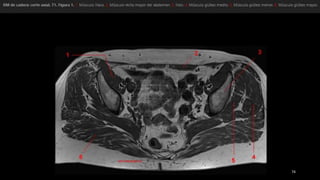

• tensor dela fascia lata (tfi), el psoasilíaco (Ips), el sartorio (sa) y el recto femoral (rf). • los vientres musculares se representan en gris y los tendones, en negro. • Punta de flecha blanca señala el tendón del recto femoral. • flecha, fascia lata.

• el tensorde la fascia lata (Tfn y el sartorio (Sa) se originan en la espina ilíaca anterosuperior (flecha recta). • recto femoral (Rf se origina en la espina ilíaca anteroinferior (punta de flecha) , • músculos ilíaco y psoasilíaco convergen en un tendón común en un punto distal que se inserta en el trocánter menor (flecha curva). • músculo pectíneo (Pe) • rama superior del pubis (Pb).

• músculo glúteomayor (GMa) • músculo tensor de la fascia lata (Tfl anterior y la fascia lata (FL) situada entre ambos músculos • «bandeleta de Massiat» (BM) • glúteo medio (GMe) y glúteo menor (GMI) • trocánter mayor (TM)